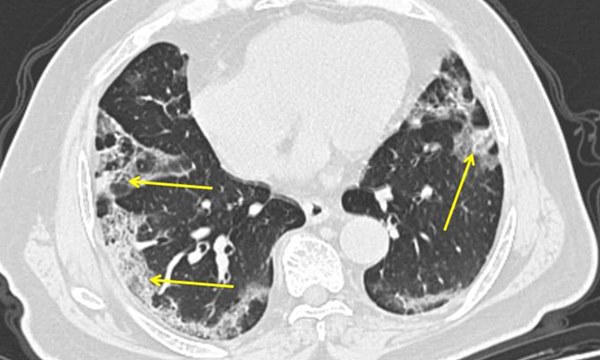

Chụp CT từ một bệnh nhân Covid-19. Các mảng mờ ở rìa ngoài của phổi (mũi tên) là phần phổi bị viêm. Ảnh: Bệnh viện Mount Sinai/AP.

Ông Wilson nói có bằng chứng cho thấy viêm phổi do Covid-19 có thể đặc biệt nghiêm trọng. Viêm phổi ở các ca nhiễm Covid-19 thường ảnh hưởng tới toàn bộ phổi, thay vì chỉ những phần nhỏ của phổi.